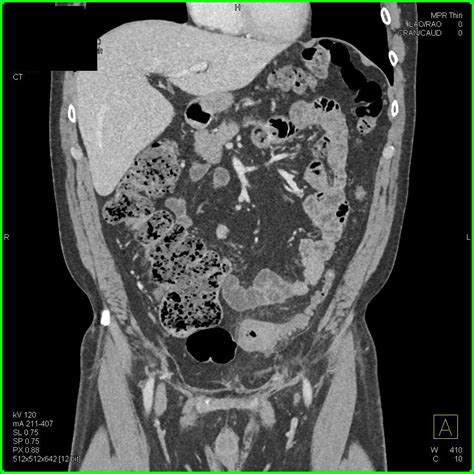

Diagnosing Diverticulitis Sigmoid Colon

Diagnosing diverticulitis sigmoid colon involves a combination of medical history, physical examination, and diagnostic tests. The diagnostic process typically includes:

• Imaging Tests: Imaging tests such as a CT scan or MRI can provide detailed images of the colon and help confirm the diagnosis.